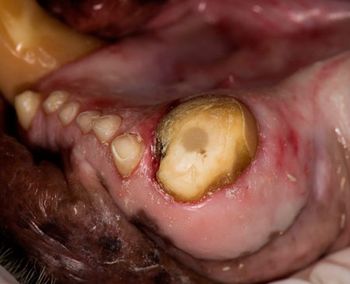

A veterinary team works together to help a police dog with two fractured maxillary canine teeth.